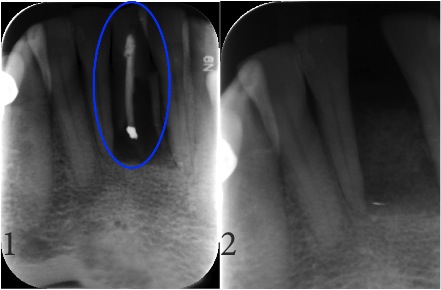

Endodontic & Implantology Associates Bone Grafting Case Study: Case C

1. Fractured Tooth (Note: Fracture visible in X-Ray)

2. Extraction of Fractured Tooth and Bone Graft

Disclaimer: Not all fractures are visible in X-Rays or have symptoms. However, if you are feeling any pain or have had any trauma please schedule a consultation with one of our specialists immediately